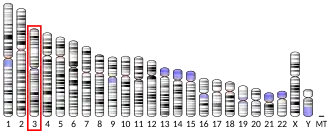

Neprilysin (/ˌnɛprɪˈlaɪsɪn/; also known as membrane metallo-endopeptidase (MME), neutral endopeptidase (NEP), cluster of differentiation 10 (CD10) and common acute lymphoblastic leukemia antigen (CALLA)) is an enzyme that in humans is encoded by the MME gene. Neprilysin is a zinc-dependent metalloprotease that cleaves peptides at the amino side of hydrophobic residues and inactivates several peptide hormones including glucagon, enkephalins, substance P, neurotensin, oxytocin, and bradykinin.[5] It also degrades the amyloid beta peptide whose abnormal folding and aggregation in neural tissue has been implicated as a cause of Alzheimer's disease. Synthesized as a membrane-bound protein, the neprilysin ectodomain is released into the extracellular domain after it has been transported from the Golgi apparatus to the cell surface.

Neprilysin is expressed in a wide variety of tissues and is particularly abundant in kidney. It is also a common acute lymphocytic leukemia antigen that is an important cell surface marker in the diagnosis of human acute lymphocytic leukemia (ALL). This protein is present on leukemic cells of pre-B phenotype, which represent 85% of cases of ALL.[5]